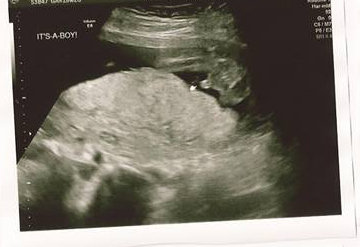

It's a healthy baby boy! His name is going to be Tristan Nicholas. Tristan's measurements are right where they should be. Everything with the baby looks great! The only concern the doctor has is they found venous lakes. They want to take a closer look at it so I've been referred to a place that has better U/S for high risk pregnancies. They want to keep an eye on it due to past pregnancy complications. Hopefully we'll get some good news when the U/S is done. We don't have a date for that yet, but the doctor said to expect a call for a date and time within the next couple days.